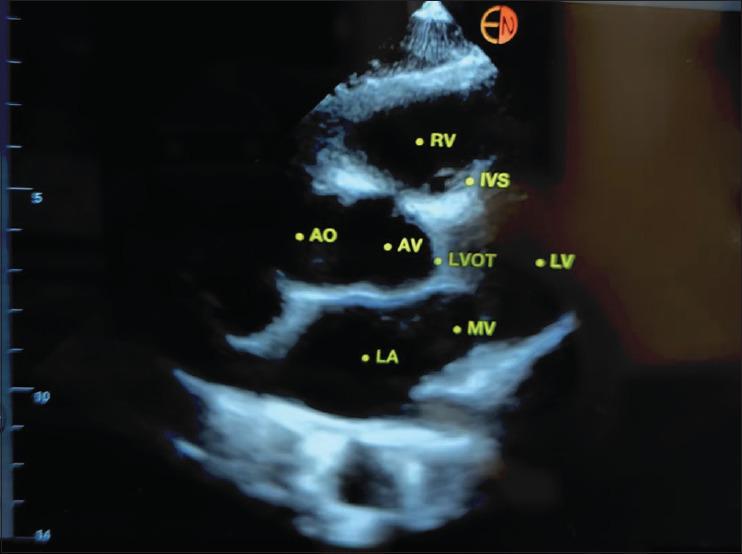

人工智能(AI)曾一度被视为前沿技术。然而,如今人工智能已渗透到各个行业,在许多方面影响着工作和家庭生活。虽然医学领域已经存在由人工智能驱动的诊断和治疗应用,但人工智能的潜力与其临床应用之间仍存在差距。本文综述了人工智能驱动的超声(US)在麻醉学和围手术期医学中的应用现状。我们对研究人工智能在围手术期超声应用的文献进行了检索。用于超声心动图和区域麻醉的人工智能应用最为成熟和发达。虽然肺部成像和血管穿刺方面也有相关应用,但气道和胃部超声成像解决方案的人工智能程序尚未出现。与人工智能应用相关的法律和伦理挑战需要随着时间的推移加以解决。人工智能应用在教育和培训方面是有益的。虽然资源匮乏地区可能会从人工智能中受益,但经济负担是一个相当大的限制因素。

优化麻醉学和围手术期医学中的人工智能超声工具:先进技术应用的新前沿。

Optimising artificial intelligence ultrasound tools in anaesthesiology and perioperative medicine: The next frontier for advanced technology application.